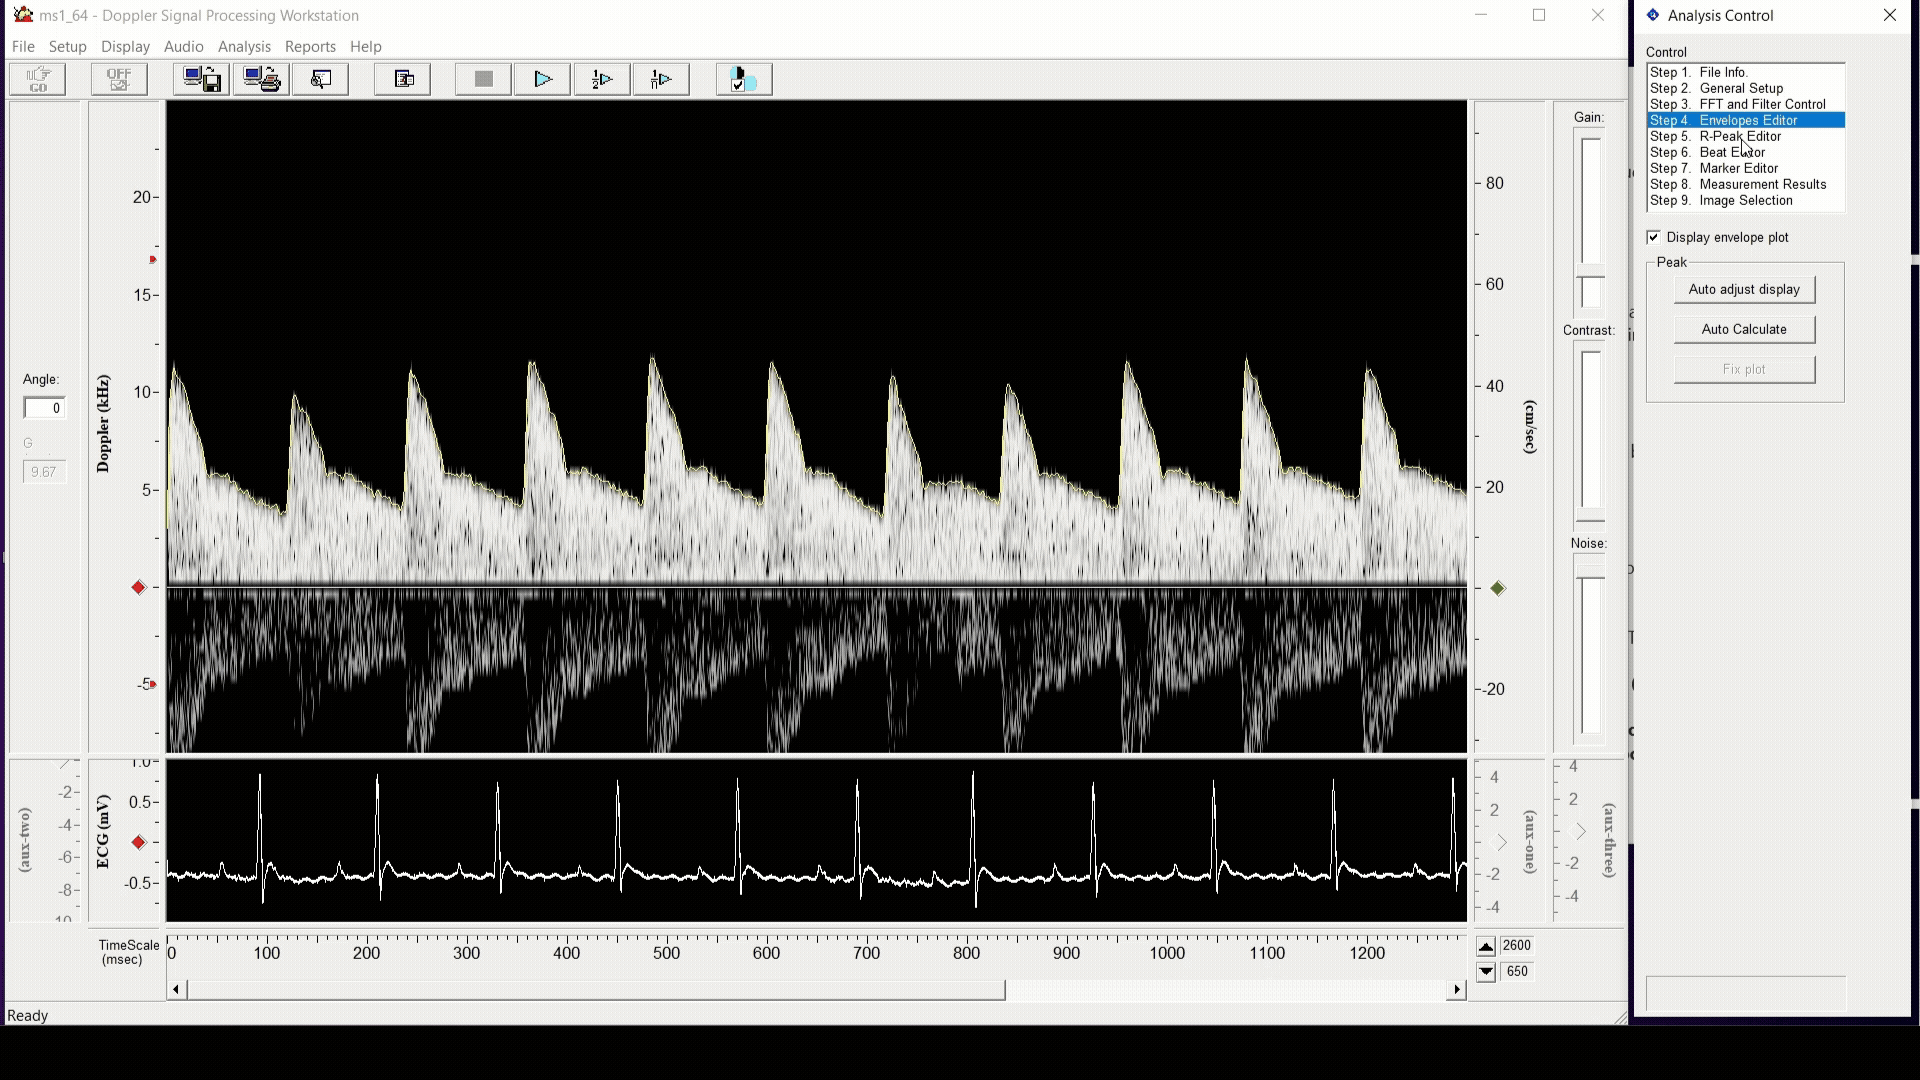

Pulsed Doppler signals from the PDT are digitized at high sampling rates by the DSD and the workstation software. The acquired signals are processed using a fast Fourier transform algorithm and displayed as real-time grayscale Doppler flow velocity spectrograms. The workstation software permits recording and analysis of these spectrograms, ideal for report generation and publication purposes. This system has been successfully used in publications with mice, rats, bats, naked mole rats and other small animals. It is also capable of measuring blood flow velocities in larger animals using our implanted extra-vascular Doppler cuff probes.

Software

The software is designed to streamline your workflow with intuitive controls that makes it easy to analyze datasets. Designed with simplicity in mind, it provides the essential tools you need to manage analysis with reliable results.